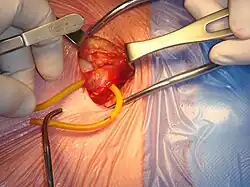

Pose de filet (plaque)

Réparation ouverte antérieure avec prothèse (Lichtenstein)

L’opération "de base" que tout chirurgien viscéral apprend pendant sa formation est encore la technique de Lichtenstein. Un filet plat est placé au-dessus du défaut[11]. C'est une réparation sans tension (tension-free) sur les muscles grâce à la présence du filet. Les complications sont rares et incluent les douleurs chroniques (<5 %), récidives (environ 2%), hématomes, séromes, infection (<1%). Comme pour toute cure de hernie inguinale, le risque existe de léser le déférent et/ou les vaisseaux testiculaires, ce qui peut produire une orchite (inflammation du testicule suivie d'atrophie), des troubles de l'éjaculation et des conséquences sur la fertilité si la lésion est bilatérale (ou la personne n'a qu'un seul testicule)[12]. Mais ce sont des situations exceptionnelles. Les troubles urinaires sont aussi des complications très rares.